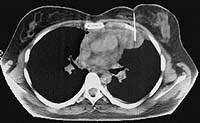

- •3.6.2. Компьютерная томография в диагностике опухолей средостения